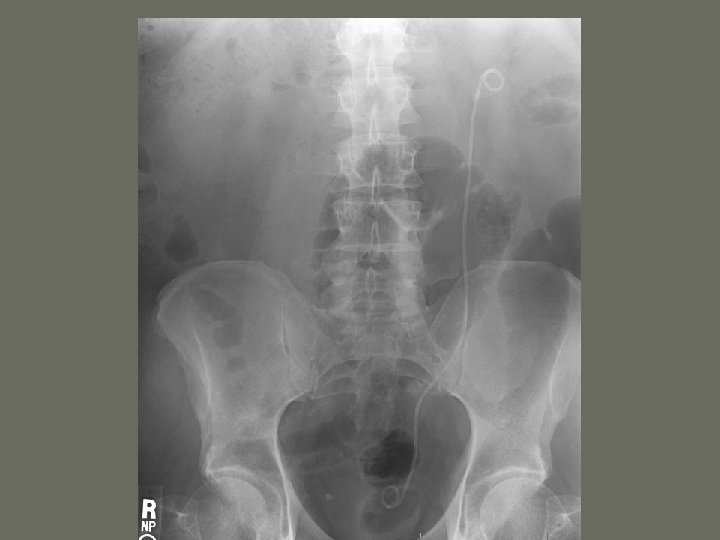

Interventional Procedures 7. Inferior vena cava filter • catches an _____ before is reaches the small vessels in the heart • prevents a pulmonary embolus

Interventional Procedures 6. Ureteric Stent Placement • Inserted in ureter • performed after a percutaneous nephrostomy • used on patients with ________ of the renal system